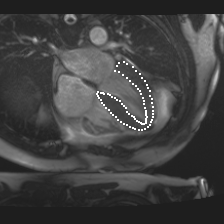

Accurate segmentation and motion estimation of myocardium have always been important in clinic field, which essentially contribute to the downstream diagnosis. However, existing methods cannot always guarantee the shape integrity for myocardium segmentation. In addition, motion estimation requires point correspondence on the myocardium region across different frames. In this paper, we propose a novel end-to-end deep statistic shape model to focus on myocardium segmentation with both shape integrity and boundary correspondence preserving. Specifically, myocardium shapes are represented by a fixed number of points, whose variations are extracted by Principal Component Analysis (PCA). Deep neural network is used to predict the transformation parameters (both affine and deformation), which are then used to warp the mean point cloud to the image domain. Furthermore, a differentiable rendering layer is introduced to incorporate mask supervision into the framework to learn more accurate point clouds. In this way, the proposed method is able to consistently produce anatomically reasonable segmentation mask without post processing. Additionally, the predicted point cloud guarantees boundary correspondence for sequential images, which contributes to the downstream tasks, such as the motion estimation of myocardium. We conduct several experiments to demonstrate the effectiveness of the proposed method on several benchmark datasets.